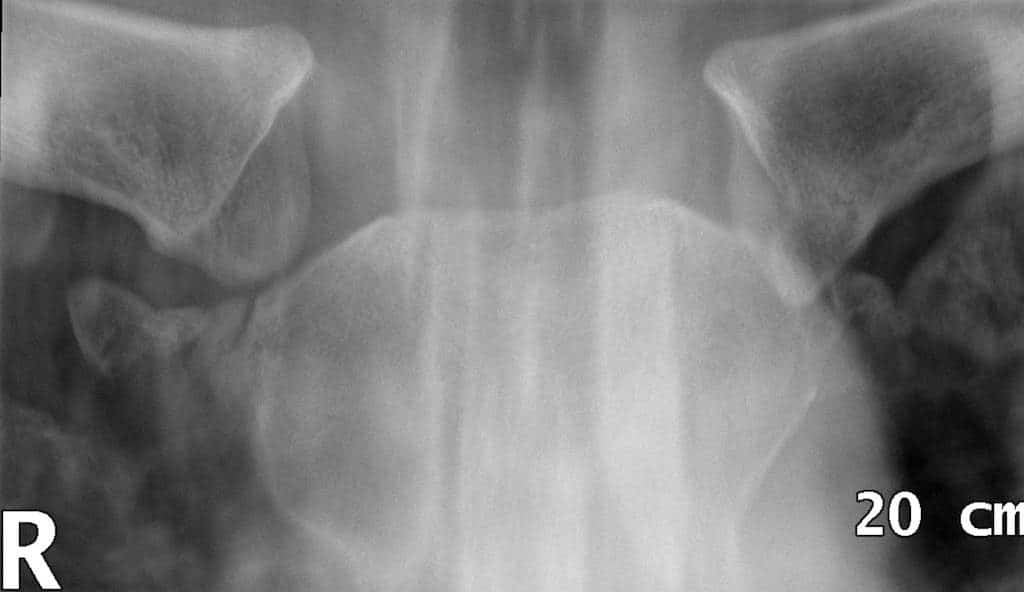

Fig 1.2 - Radiograph of an sternoclavicular joint dislocation.

Fig 3

Radiograph of a right sternoclavicular joint dislocation.